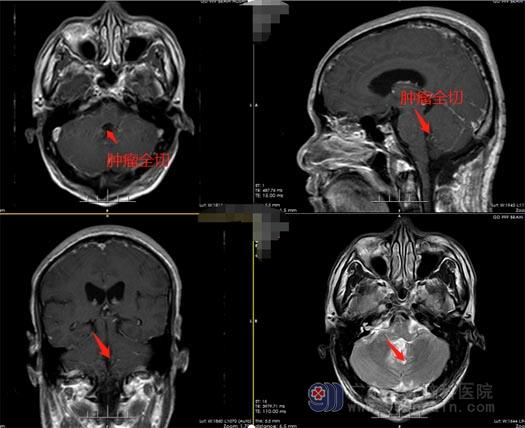

在排除手术相关禁忌症后,广东三九脑科医院鲁明副院长带领神经外五科团队为郭先生实施了四脑室占位病变切除术。幸运的是,郭先生手术肿瘤全切,神经、血管、脑组织均保护完好。术后郭先生神志清醒,因术中周围颅神经、血管保护良好,郭先生无不良并发症出现,恢复很快。

神经外五科王国良主任介绍,一旦第四脑室出现肿瘤,并开始生长,则第一个受到影响的是脑脊液循环;阻塞其通路后,会出现颅内高压症状,主要表现为头痛头晕,呕吐,胃口不好,肢体无力等。因此,患者需及时就医,并选择最佳的个体化治疗方案,在切除肿瘤的同时,尽量保留患者的神经功能。